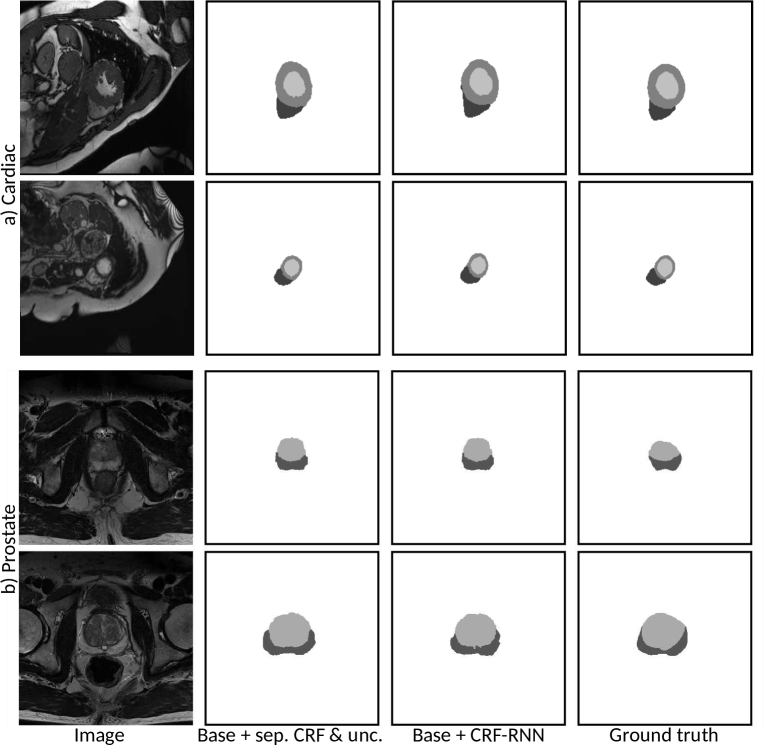

The Dice scores with respect to the reference annotations for all the examined methods and structures are shown in Table 1. Note that ACDC challenge server did not allow for higher precision Dice reporting in the post-challenge phase. Example segmentations for the two best performing methods are shown in Fig. 3 for the cardiac and prostate data, respectively.

Refer to caption

Figure 3: Randomly sampled example segmentations for the two best performing training strategies for the a) cardiac and b) prostate data.